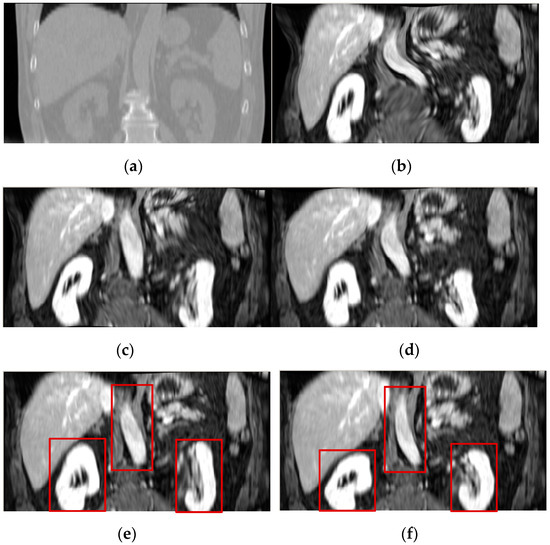

Figure 9 visually shows the registration results of 3D PD-T1 images for all the evaluated methods. Here, it should be noted that the background regions in these images are removed and the same operation will be implemented for other experiments in the rest of this paper. The comparison among Figure 9f and Figure 9c–e shows that the registration result of the FMIND method is more similar to the reference image that is shown in Figure 9a than those of the ESSD, MIND, and HLCSO methods. Especially for the tissue indicated by the red boxes in Figure 9, the FMIND can recover its deformation better than other evaluated methods.

Figure 9.

The registration results of all evaluated methods operating on 3D PD-T1 images. (a) PD image (reference image); (b) T1 image (float image); (c) ESSD; (d) MIND; (e) hybrid L-BFGS-B and cat swarm optimization (HLCSO); and, (f) FMIND.